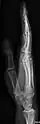

• Fingers - DP and Lateral

• Thumb - AP and Lateral